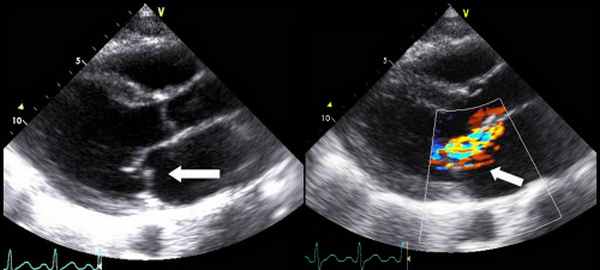

- ЭхоКГ. ЭХОКГ позволяет определить: структуру клапана (двустворчатый клапан, утолщение створок, фиброз, кальциноз, вегетации), характер его движения (подвижность створок, степень открытия) и площадь отверстия; изменения корня аорты (постстенотическая дилатация), объем левого желудочка, выраженность гипертрофии левого желудочка, нарушения локальной сократимости левого желудочка (указывающие на ИБС), ФВ, объем левого предсердия, состояние других клапанов. Доплеровское исследование позволяет с высокой точностью определить градиент давления между аортой и левым желудочком.

Митральная регургитация

• Vena contracta ≥7 мм.

• Эффективная площадь отверстия регургитации EROA ≥40 мм².

• Объем регургитации ≥60 мл.

• Фракция регургитации ≥50%.

• Конечно-систолический диаметр левого желудочка ≥40 мм.

• Диаметр левого предсердия ≥55 мм или объем ≥60 мл/м².